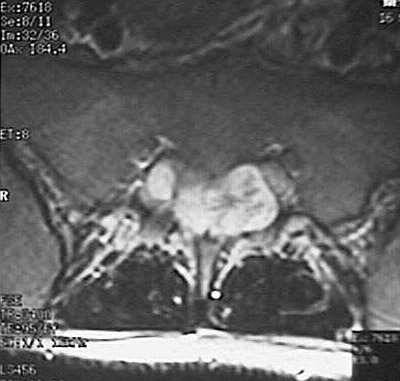

Below is a transverse MRI scan that reveals the lobulated ependymoma.